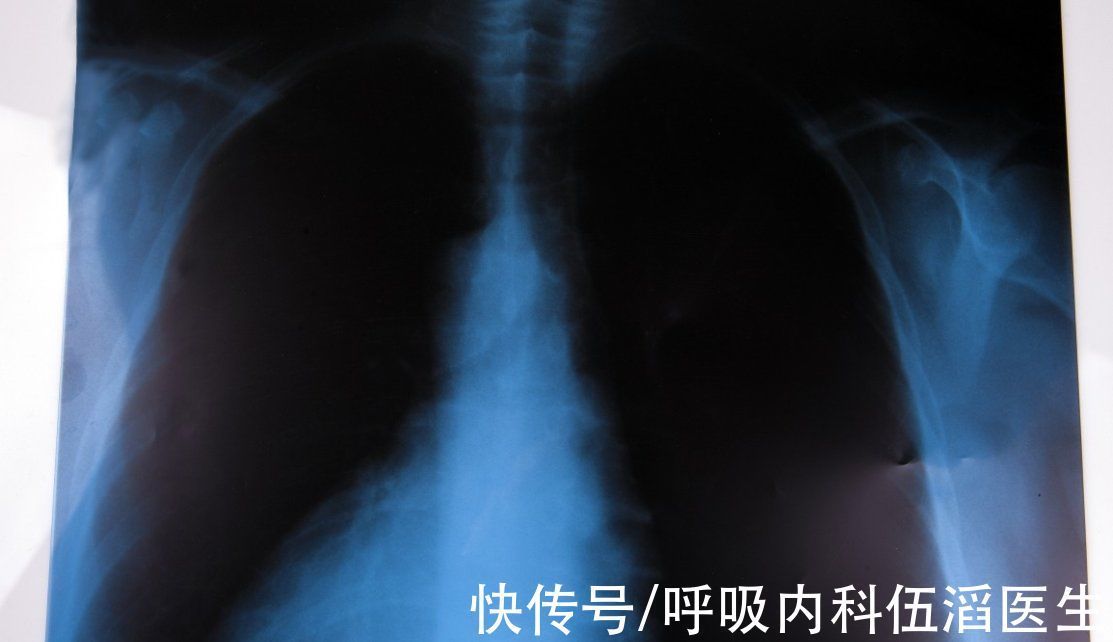

我是一名90后的宝妈,因为结婚的晚,孩子也才刚刚一岁,就在去年的一次公司体检里,体检中我的肺部ct显示我的肺部有一团阴影,首先那个医生怀疑是肺结核,要我马上去医院具体检查一下,最后结果是肺部结节。

【 毛玻璃|查出肺结节,就意味着癌变的前兆吗?一名肺结节患者的亲身经历】因为数量很多,所以我想尽快做手术切除。其实最开始知道自己有肺结节的时候,我的心情特别复杂,平时生活习惯还算健康,也没什么不良的嗜好,我很好奇为什么会得肺结节呢?而且还是毛玻璃肺结节,可能是因为太焦虑了,那段时间我开始失眠了,整个人白天也没什么没精神,连工作的时候同时也经常会说:从来没有见过你这副样子,病恹恹的。

相信大多数人在查出肺结节后,要么就是不以为然要么就是特别担心,其实肺结节并不是可怕的疾病,而且绝大部分甚至都不需要治疗,那么我们该如何判断肺结节有没有癌变的倾向呢?

肺结节根据肺部影像特点能分为三种

1、实性的结节

这种结节会完全遮盖肺实质,首先就是它往恶性发展的概率了,一般小于6毫米的低风险实性结节只要每年复查就行,只要结节不生长是不需要进行手术的,中风险的结节则需要半个月检查一次,再次评估风险等级,如果是高风险的实性结节则建议直接进行切除手术。

2、部分实性结节